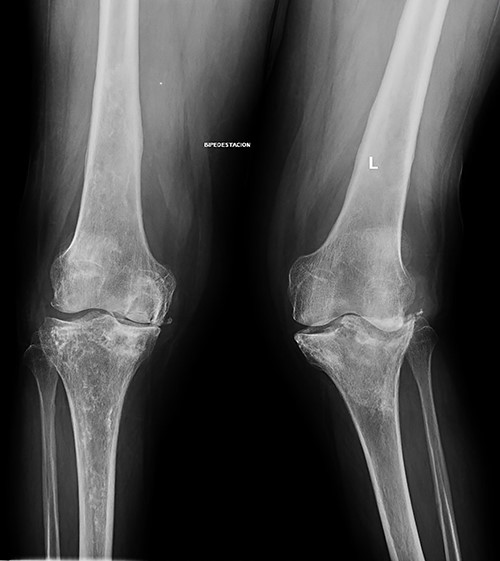

At this point, the patient was recovering from a respiratory infection with multiple admissions and relapses, with CD4 cell count of 146 cells/ml. Therefore, conservative treatment was recommended, but pain control was insufficient. After 8 months she was admitted to the emergency service in a wheelchair due to intractable acute pain without prior trauma in the left knee, which prevented weight-bearing. New standing X-rays of the left knee showed collapse of the external tibial plateau (Fig. 2). At this time, the patient exhibited acceptable medical control, with CD4 240 cells/ml and undetectable viral load.

Standing X-rays of the left knee 8 months later showed collapse with depression of the external tibial plateau and associated bone defect that caused 28° valgus deformity.